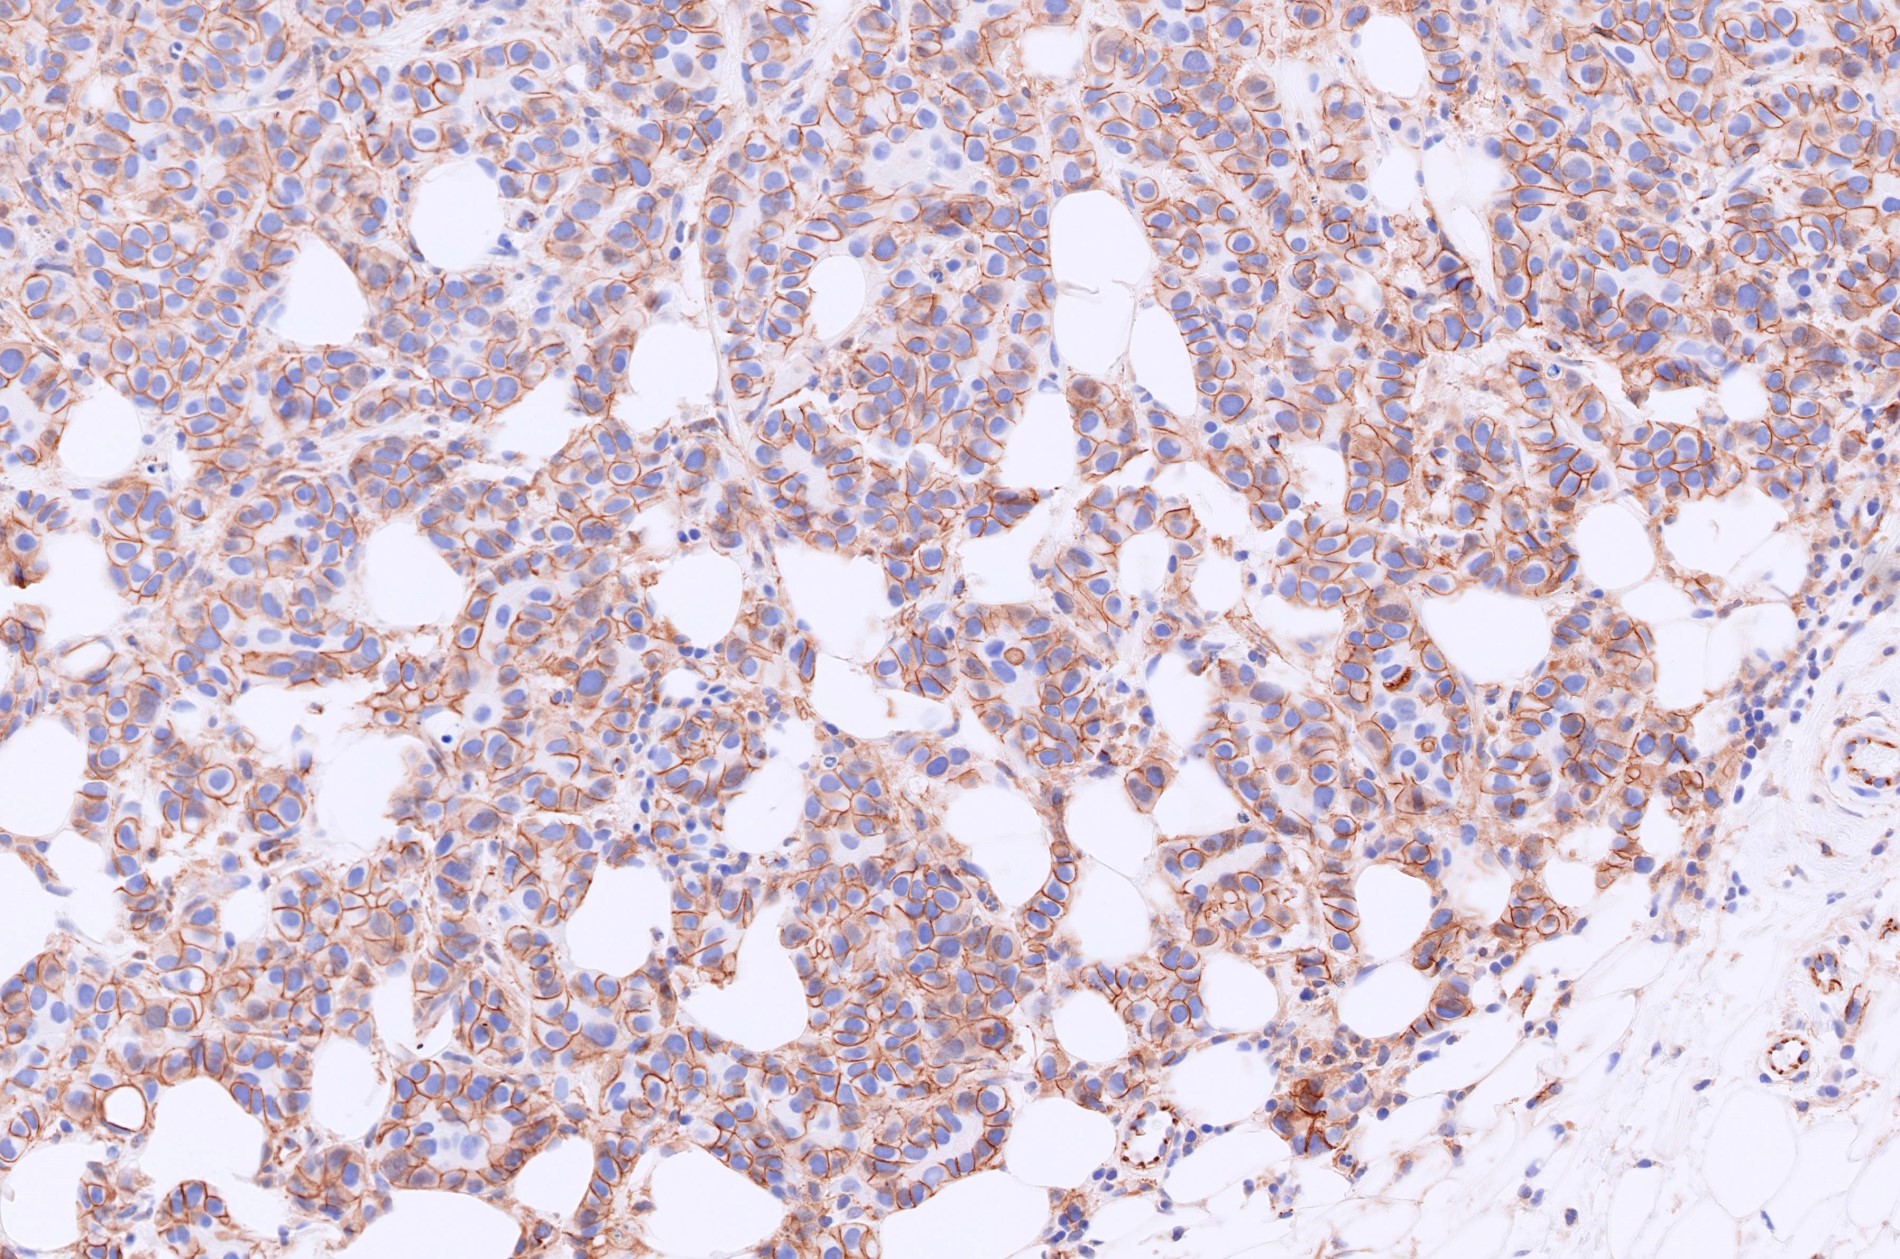

Microscopic (histologic) images

Contributed by Julie M. Jorns, M.D., Kristen E. Muller, D.O., Gary Tozbikian, M.D. and Emad Rakha, M.D.

- Angiolymphatic invasion in 35%; differs from tissue retraction because:

- Endothelial lining is present and is CD31+, ERG, D2-40+, CD34+ and factor VIII+

- Luminal low molecular weight cytokeratins (CK8 / 18, CK19 and CK7 and pancytokeratins such as AE1 / AE3, CAM 5.2, MNF-116), EMA, E-cadherin, p120, ER (60 - 80%), PR (50 - 70%), HER2 (15 - 20%) (Am J Clin Pathol 2006;125:377)